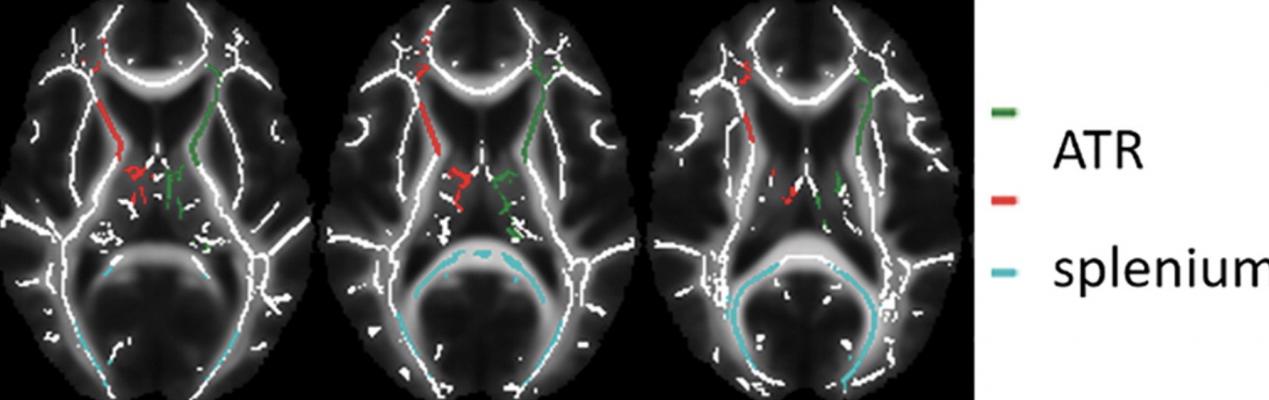

Images of regions of interest (colored lines) in the white matter skeleton representation. Data from left and right anterior thalamic radiation (ATR) were averaged. Image courtesy of C. Bouziane et al.

Patients received either MPH or a placebo for 16 weeks. Before and one week after treatment cessation, the participants underwent magnetic resonance imaging (MRI) including diffusion tensor imaging (DTI), a technique that helps assess white matter. DTI provides a measure called fractional anisotropy (FA), which is thought to reflect important aspects of white matter such as nerve fiber density, size and myelination — the process of coating nerve fibers to protect the nerve and help it carry signals more efficiently.

In boys with ADHD, four months of treatment with MPH was associated with increased white matter FA. The effects were age-dependent, as they were not observed in adults treated with MPH.